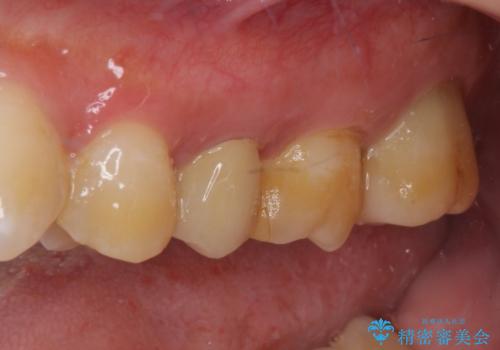

来院されたときには、神経を全て取り除くことになるであろうと思っていらっしゃいましたが、結果としては歯根部分の歯髄を残すことができました。

後日状態を確認したところ、残された神経に異常は認められませんでした。

欠損歯質は比較的小さかったため、セラミックインレーにて修復治療を行いました。